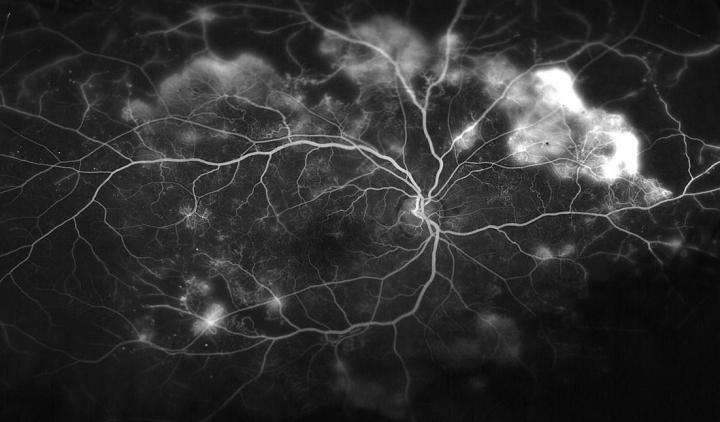

The disease, diabetic retinopathy , is the most common cause of vision loss in working-age adults in the United States. Diabetic eye disease occurs when the normal blood vessels in the eye are replaced over time with abnormal, leaky, fragile blood vessels that leak fluid or bleed into the eye, damaging the light-sensitive retina and causing blindness. Forty to 45 percent of Americans with diabetes have diabetic retinopathy, according to the National Eye Institute.

Laser-sealing eye blood vessels can save central vision, but this often sacrifices peripheral and night vision, according to Akrit Sodhi, M.D., Ph.D. , an assistant professor of ophthalmology at the Johns Hopkins University School of Medicine. Several recently developed drugs -- bevacizumab, ranibizumab and aflibercept -- can help treat these blood vessels by blocking the action of VEGF, a so-called growth factor released as part of a chain of signals in response to low oxygen levels, which stimulates the growth of new, often abnormal, blood vessels. But studies have shown that although these drugs slow progression to proliferative diabetic retinopathy, it does not reliably prevent it.